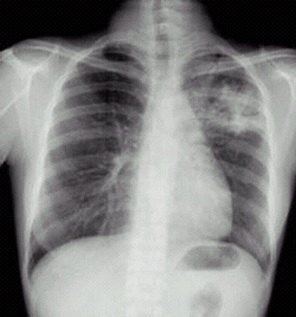

03卷-3.病史:男性,34歲,咳嗽、無痰半月,伴低熱。診斷(本題滿分2.00分)

A.左上支氣管擴(kuò)張

B.左上肺炎

C.左上浸潤型肺結(jié)核

D.左側(cè)胸腔積液

本題答案:C

題目解析:【該題針對(duì)“X線-浸潤型肺結(jié)核”知識(shí)點(diǎn)進(jìn)行考核】